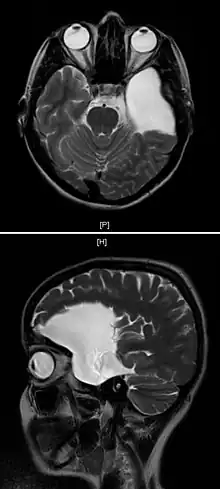

| Arachnoid cyst | |

| An MRI of a 25-year-old woman with left frontotemporal arachnoid cyst. | |